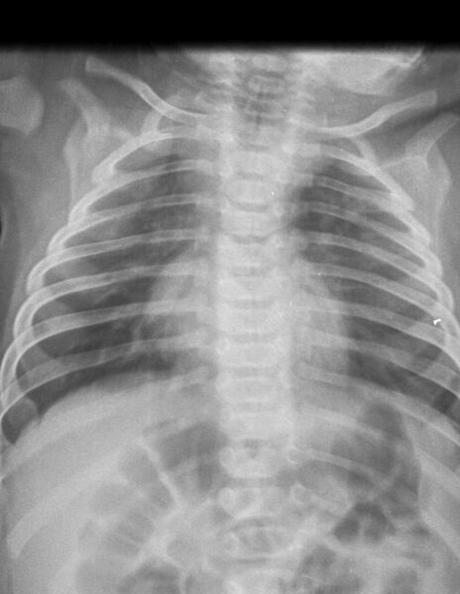

AP de tórax

EN LA PROYECCIÓN RADIOGRÁFICA OBTENIDA MUESTRA LOS SIGUIENTES HALLAZGOS:

Tejidos blandos simétricos, sin cambios en su densidad.

Silueta cardiomediastinica de forma habitual.

Botón aórtico, con diámetros adecuados, sin identificar calcificaciones.

Tráquea con leve desviación hacia la derecha, columna vertebral central.

Trama broncovascular aumentada, de predominio derecho.

Hilios pulmonares, de aspecto adecuado.

Campos pulmonares, con presencia de imágenes que simulan ser micronódulos, en lóbulo superior es como de predominio derecho.

Recesos cardiofrénicos y costo frénicos se observan libres.

Estructuras óseas, sin evidencia de lesiones líticas, blásticas o perdidas de la contigüidad. Fisis de crecimiento acorde a la edad.

IMPRESIÓN DIAGNOSTICA:

EN EL PRESENTE ESTUDIO RADIOGRÁFICO, CON IMÁGENES SUGERENTE DE PROCESO VIRAL RESPIRATORIO, PROBABLEMENTE BRONQUIOLITIS.

CORRELACIONAR CON DATOS CLÍNICOS Y ANTECEDENTES DE CONSIDERARSE NECESARIO POR MÉDICO TRATANTE, COMPLEMENTAR CON ESTUDIOS ADICIONALES O DE CONTROL, SEGÚN EVOLUCIÓN CLÍNICA DEL PACIENTE.